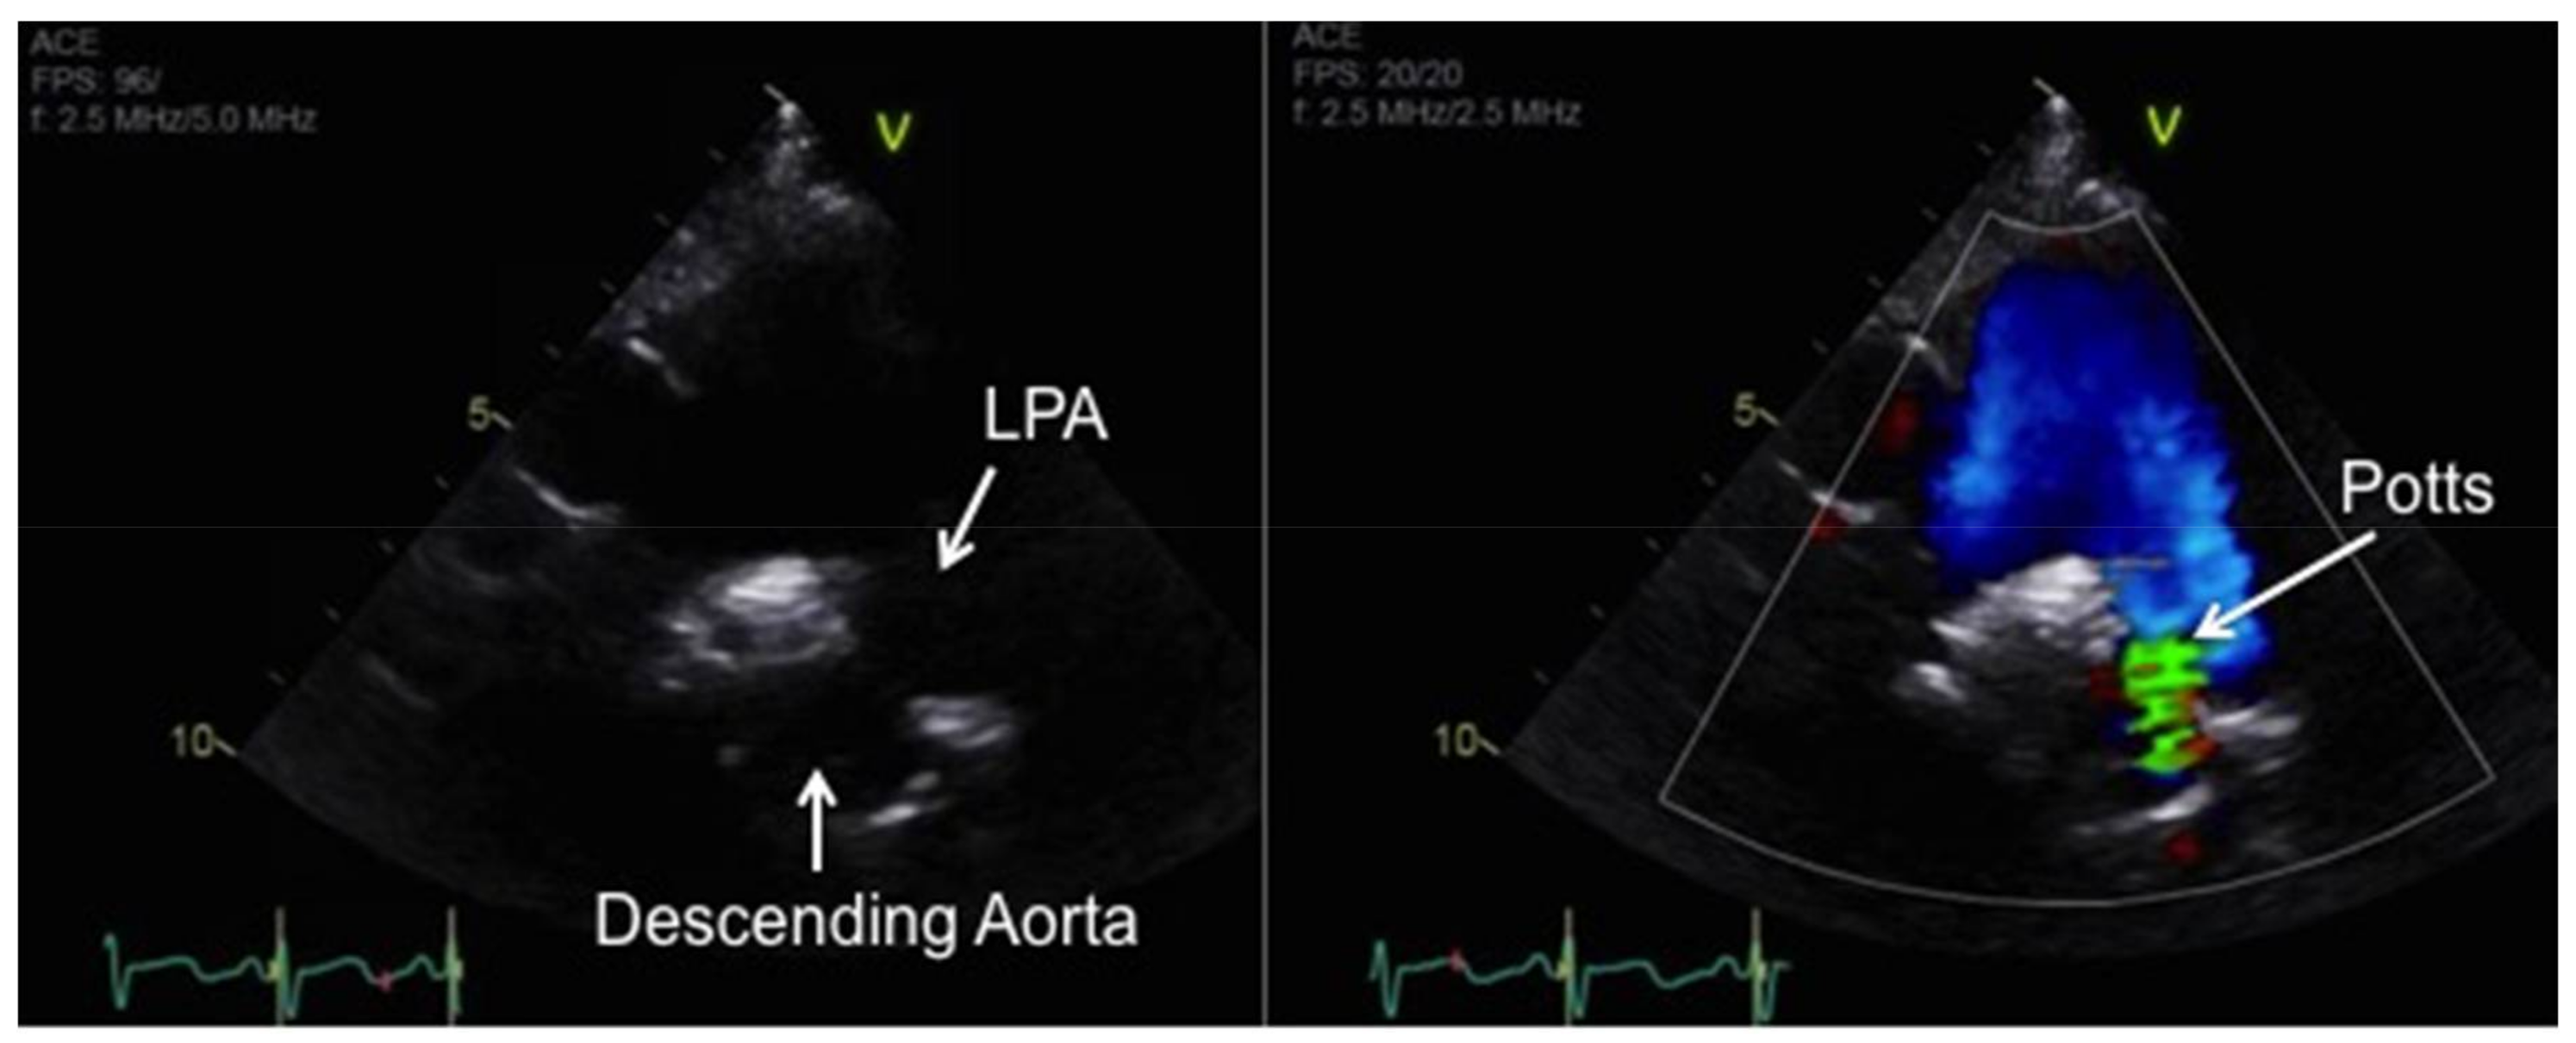

- Baruteau, A.E.; Serraf, A.; Levy, M.; Petit, J.; Bonnet, D.; Jais, X.; Vouhé, P.; Simonneau, G.; Belli, E.; Humbert, M. Potts shunt in children with idiopathic pulmonary arterial hypertension: Long-term results. Ann. Thorac. Surg. 2012, 94, 817–824. [Google Scholar] [CrossRef] [PubMed]

- Blanc, J.; Vouhe, P.; Bonnet, D. Potts shunt in patients with pulmonary hypertension. N. Engl. J. Med. 2004, 350, 623. [Google Scholar] [CrossRef] [PubMed]

- Grady, R.M.; Eghtesady, P. Potts Shunt and Pediatric Pulmonary Hypertension: What We Have Learned. Ann. Thorac. Surg. 2015, 101, 1539–1543. [Google Scholar] [CrossRef] [PubMed]